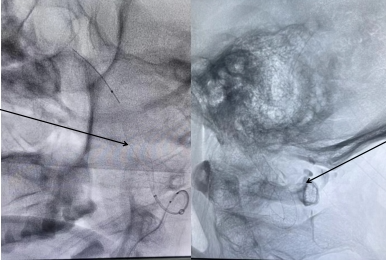

脑外科针对患者病情迅速开通了绿色急救通道,由田德洲主任主持,经北医三院韩金涛教授,延安分院脑外科陈素华学术主任、董永军副主任各位专家远程讨论给出了最佳治疗方案,决定在全身麻醉下行 SurpassEvolve 血流导向密网支架植入术。

与家属积极沟通后,术中北京驻延 麻醉科 专家韩永正主任采用不插管全麻,由北医三院韩金涛教授指导延安市中医医院脑外科团队为患者实施了手术。